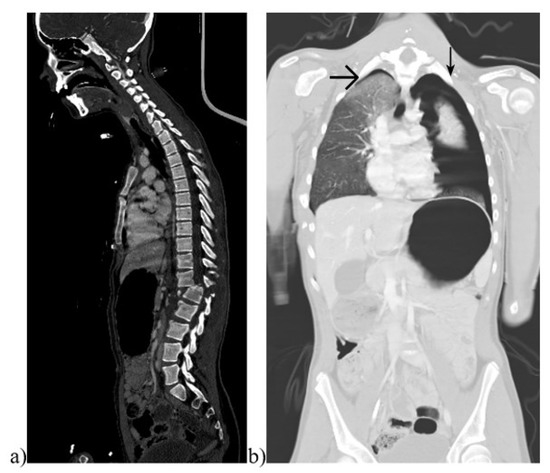

Figure 1.

Images of a pediatric whole-body computed tomography (WBCT). Example of a 14-year-old girl with a traffic accident as a passenger in a car. CT images showing (a) a luxation fracture T12/L1 on sagittal plain in a bone window and (b) a pulmonary contusion and bilateral pneumothoraces on coronal plain in a lung window (marked by arrows).